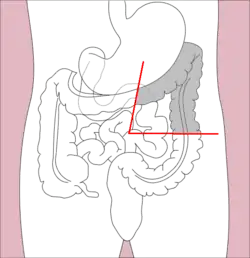

Right hemicolectomy and left hemicolectomy refer to the resection of the ascending colon (right) and the descending colon (left), respectively. When middle colic vessels and transverse colon are also resected, it may be referred to as an extended hemicolectomy.[20] Left hemicolectomy is most commonly indicated for cancer in the splenic flexure or descending colon, diverticular disease of the descending colon, and colovesicular or colovaginal fistulas that develop as a consequence of diverticular disease.[11] The main limitation to performing a left extended colectomy is the difficulty of achieving a colorectal anastomosis afterward. Different techniques, such as Deloyer's or Rosi-Cahil's techniques, have been proposed to solve this issue.[21] Right hemicolectomy is most commonly indicated for masses in the right, or ascending, colon but may also be performed for neoplasms of the cecum or appendix. Right-sided diverticulitis, cecal volvulus, inflammatory bowel disease, and adenomatous polyps are benign conditions that may require right hemicolectomy.[11]